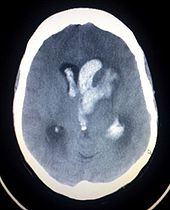

Stroke is diagnosed through several techniques: a neurological examination, CT scans (most often without contrast enhancements) or MRI scans, Doppler ultrasound, and arteriography. The diagnosis of stroke itself is clinical, with assistance from the imaging techniques. Imaging techniques also assist in determining the subtypes and cause of stroke. There is yet no commonly used blood test for the stroke diagnosis itself, though blood tests may be of help in finding out the likely cause of stroke.

Imaging

For diagnosing ischemic stroke in the emergency setting:

- CT scans (without contrast enhancements)

- sensitivity= 16%

- specificity= 96%

- MRI scan

- sensitivity= 83%

- specificity= 98%

For diagnosing hemorrhagic stroke in the emergency setting:

- sensitivity= 89%

- specificity= 100%

- sensitivity= 81%

For detecting chronic hemorrhages, MRI scan is more sensitive.